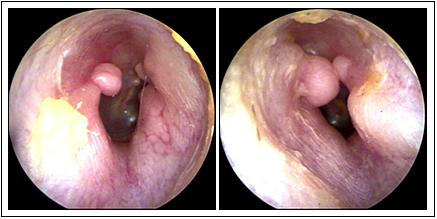

JFC otopatía supurativa crónica inactiva (der) y con colesteatoma atical (izq)